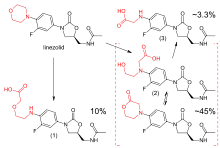

Linezolid is metabolized in the liver, by oxidation of the morpholine ring, without involvement of the cytochrome P450 system. This metabolic pathway leads to two major inactive metabolites (which each account for around 45% and 10% of an excreted dose at steady state), one minor metabolite, and several trace metabolites, none of which accounts for more than 1% of an excreted dose.[100] Clearance of linezolid varies with age and gender; it is fastest in children (which accounts for the shorter half-life), and appears to be 20% lower in women than in men.[4][100][101] There is a strong correlation between linezolid clearance and creatinine clearance.[102]